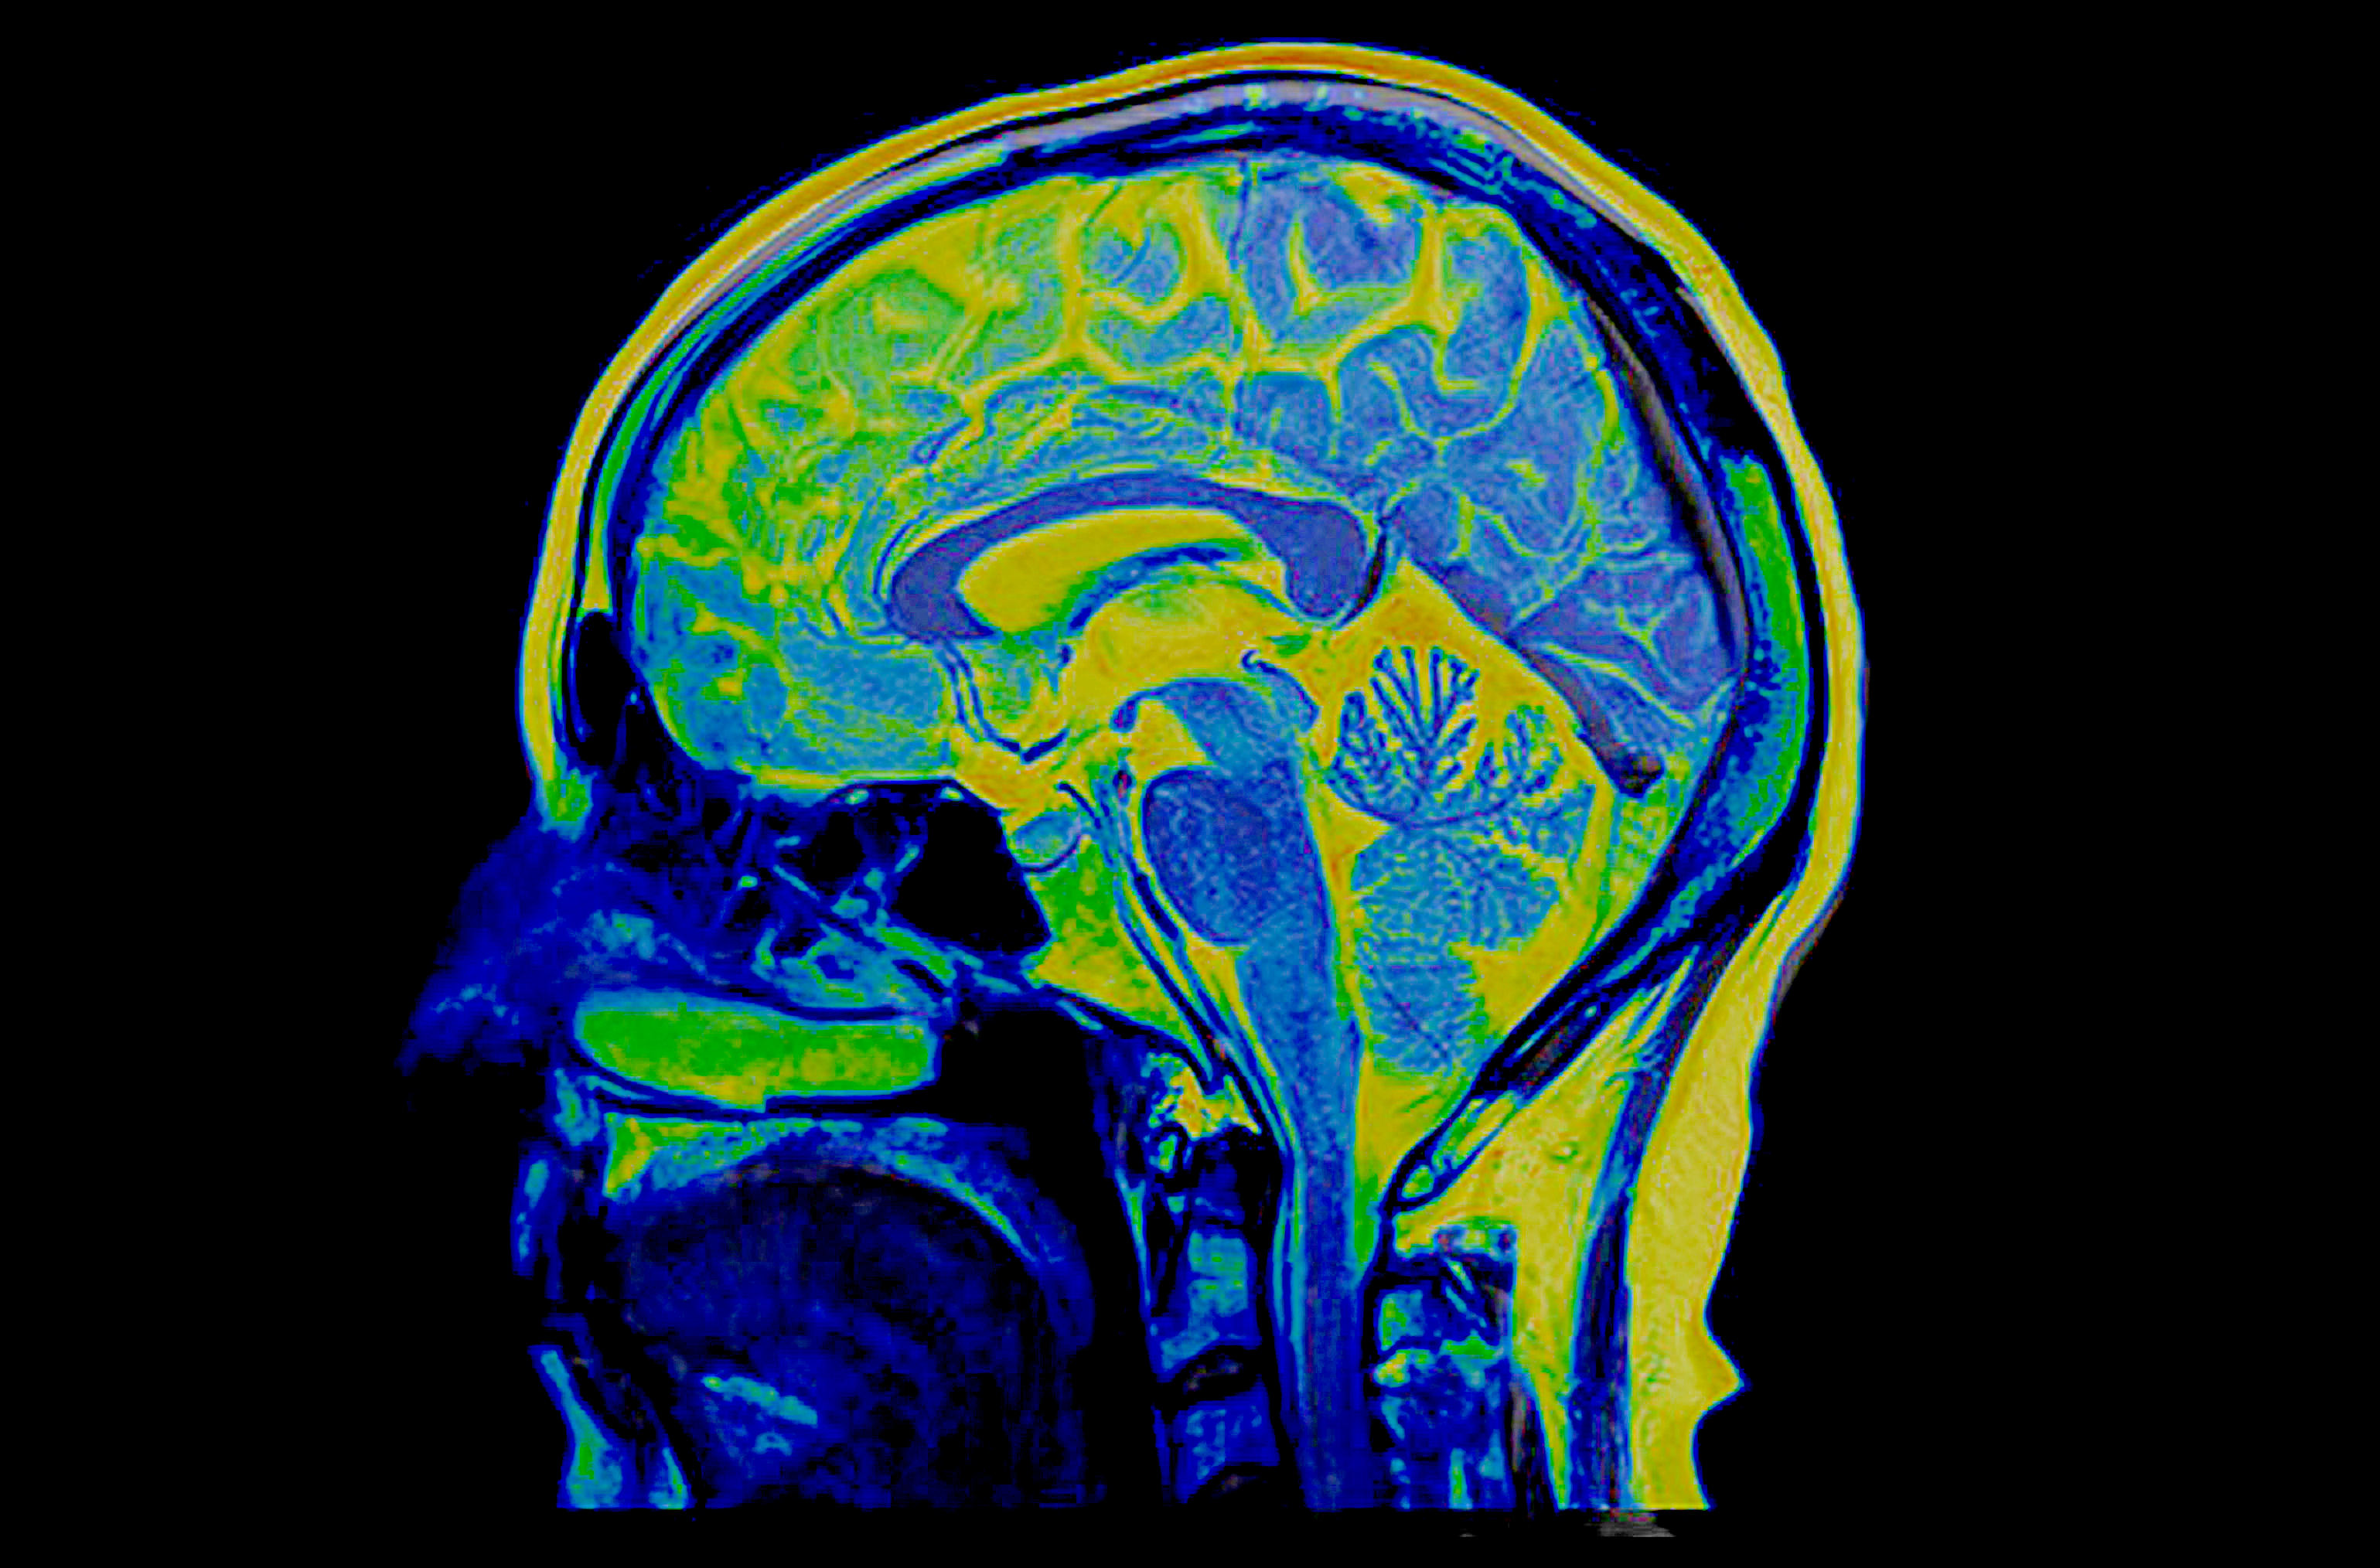

Шум в голове мрт головы

Шум в голове мрт головы 132 фотографий